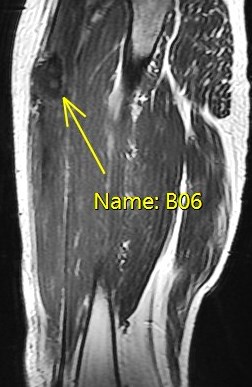

25 y/o work injury, soccer injury.

Maybe his soccer playing is his work? Who am I to ask questions. The indirect head goes on to form the central tendon. There is complete failure of the proximal myotendinous junction and there is an interposed acute hematoma. The hematoma is almost isointense to muscle. Reference article.

rectus femoris indirect head proximal myotendinous junction tear with hematoma( RID2698 )